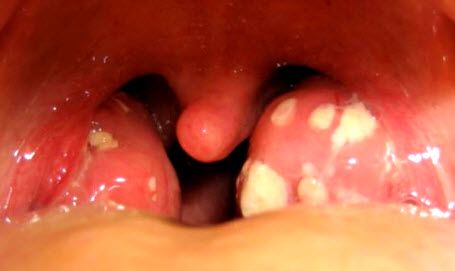

В зависимости от локализации гнойного содержимого в области миндалин различается несколько видов болезни. На фото можно заметить, если гной накапливается на поверхности миндалин, образуя пробки, то это считается фолликулярная ангина.

А на втором фото видно, что если скопление гноя происходит внутри гланд или в их мягкой и рыхлой ткани, то это лакунарная ангина .

Вид глотки больного при хроническом тонзиллите